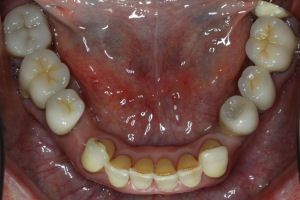

This is an advanced set of dental procedures best carried out by prosthodontists or restorative dentists. Full mouth rehabilitation is a term used in dentistry for rebuilding teeth and supporting structures after decay and gum disease has been stabilised. Full mouth rehabilitation is only required if your bite has collapsed or you have multiple missing or heavily filled teeth. Implants, crown and bridgework and/or partial or full dentures can be used to restore your bite close to its original height. Temporary restorations or dentures are used to get an idea of what the final result will be like before having the final restorations made. Temporary restorations also allow you to have input into your appearance and smile giving you the opportunity to show friends and family what your teeth may look like when the work is complete.

Before/After